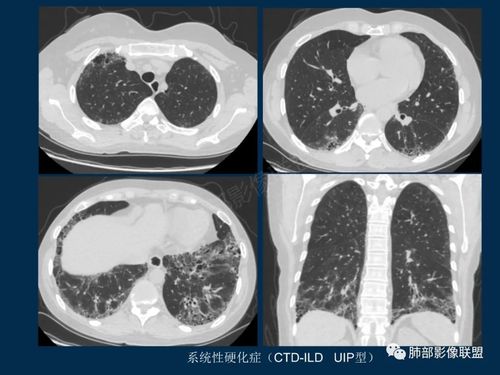

间质性肺炎影像学,间质性肺炎肺纤维化

结缔组织病继发间质性肺炎的影像学特点 不同的结缔组织病,继发的间

间质性肺炎肺纤维化

间质性肺炎ct

间质性肺炎ct表现

间质性肺炎ct图片

间质性肺炎ct图片特点